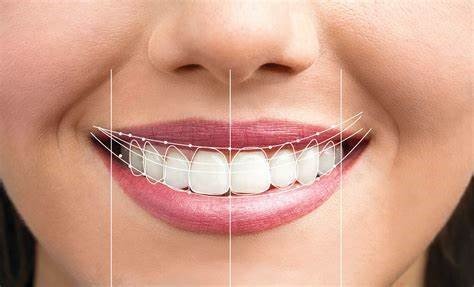

- Aesthetic Analysis

- Digital Smile Design Protocol

- Facial reference lines (interpupillary, commissural lines)

- Golden proportion assessment (ideal width-to-length ratio: 75-80%)

- Dental midline evaluation relative to facial midline (deviations <2mm generally acceptable)

- Gingival zenith positions and symmetry

- Incisal edge position and anterior guidance evaluation